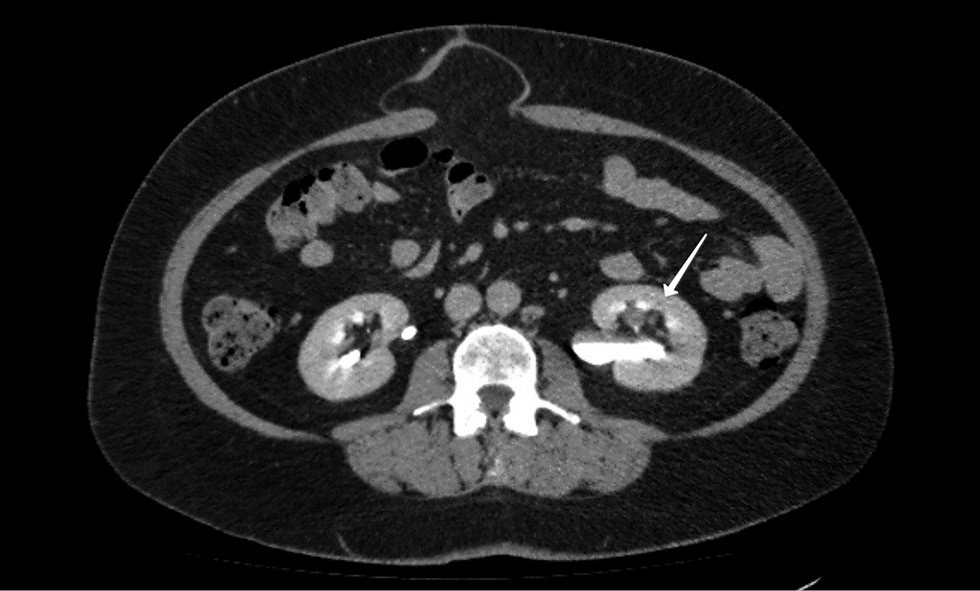

Рис. 3. Компьютерная томография органов брюшной полости. Стрелками указаны мочеточники, слева определяется уретерэктазия

Fig. 3. Computed tomography of the abdominal organs. The arrows indicate the ureters; ureterectasia is visualized on the left

По данным контрольной КТ от 17.03.2022: в левой половине малого таза над мочевым пузырем определяется конгломерат петель кишки, заполненный содержимым, не отделимый от стенки мочевого пузыря, утолщенной и накапливающей рентгенконтрастный препарат. В просвете мочевого пузыря обнаружен воздух (рис. 2.). Отмечен отек внутритазовой клетчатки, расширение тазовых сплетений слева. Дистальный отдел левого мочеточника теряется в инфильтрате, присутствует умеренная левосторонняя пиелоуретероэктазия (рис. 3, 4).